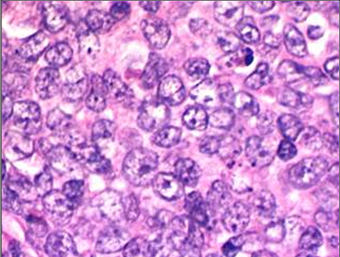

Which type of round cell tumour is this? Sheets of rounds cells with very large nucleoli

Answer

• Mast cell tumour

• Plasmacytoma

• Histiocytoma

• Lymphoma